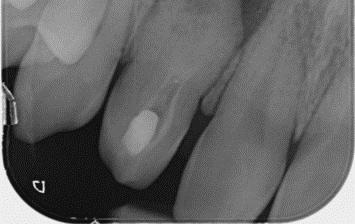

A six-month clinical and radiographic follow-up demonstrated a successful outcome. The patient was asymptomatic with no tenderness, and the previously present sinus tract had resolved. Radiographic evaluation revealed a significant reduction in the periapical radiolucency, indicating healing of the chronic apical abscess.

In conclusion, this case underscores the critical role of meticulous chemomechanical preparation of both the main and invaginated canal systems, the strategic use of appropriate intracanal medicaments, and the application of tailored obturation techniques, such as thermoplasticized gutta-percha for complex anatomies, in achieving successful endodontic outcomes in challenging DI cases. While CBCT is a valuable diagnostic tool, this case highlights that thorough clinical assessment combined with carefully interpreted conventional radiographs can be sufficient for diagnosis and treatment planning in younger patients. Ultimately, a strong foundation in basic endodontic principles and the ability to adapt treatment strategies to the unique anatomical complexities of Dens Invaginatus remain paramount for successful management.

X-Ray 5: The six-month follow-up radiograph demonstrates a significant decrease in the dimensions of the radiolucent area, consistent with a favourable outcome of the endodontic treatment.